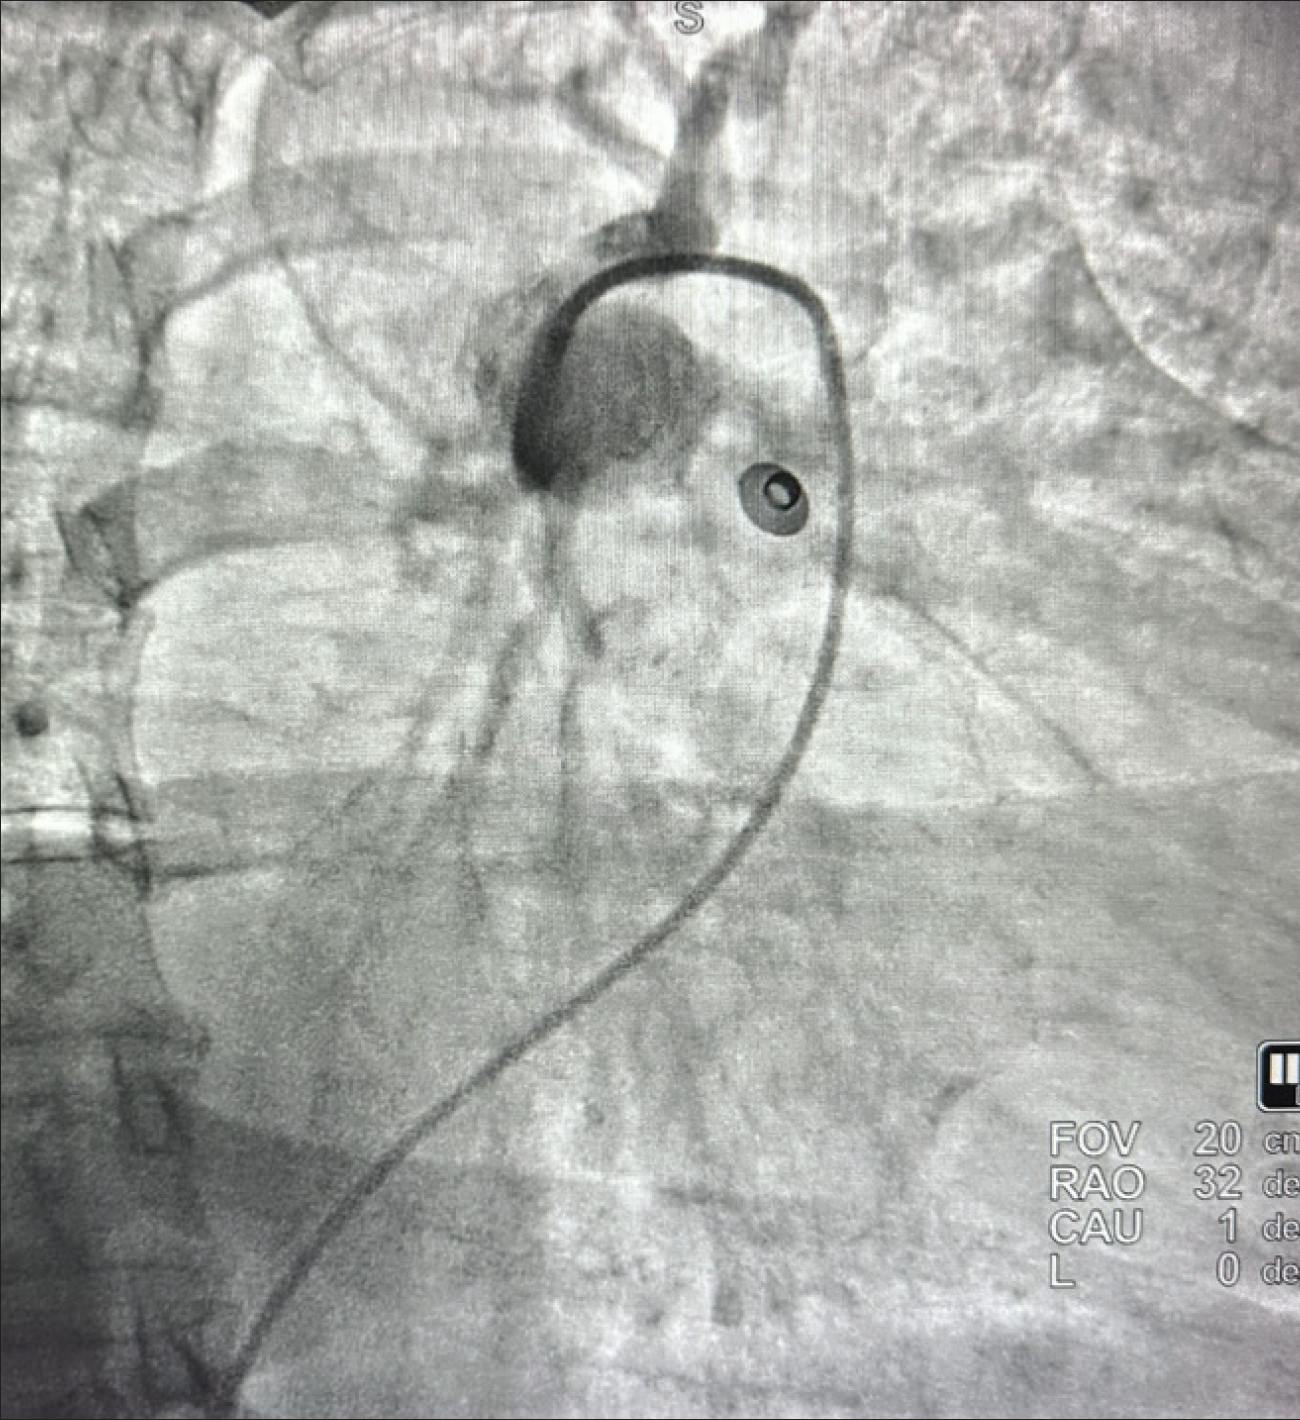

In the emergency department, she was tachycardic at 120 bpm with a systolic blood pressure of 100 mm Hg. She required 40% high-velocity oxygen support and was assessed as clinically unstable. Echocardiography revealed a hyperdynamic left ventricle, a dilated right ventricle with moderately to severely reduced function, and McConnell sign, consistent with PE (Figure 1). CTA showed a high RV/LV ratio of 1.4 and extensive left PE with possible saddle thrombus (Figure 2). The patient became progressively unstable and was administered thrombolytic therapy with tissue plasminogen activator. Overnight, her oxygen requirement improved to 6 L via nasal cannula, although she remained dyspneic and relatively hypotensive. Intravenous heparin was continued, and she was referred to interventional cardiology for further management with CAVT using Penumbra’s Lightning Flash 2.0.

Figure 1. Echocardiogram of dilated right ventricle.

Figure 2. CT revealing high RV/LV ratio of 1.4 and extensive PE with saddle thrombus.